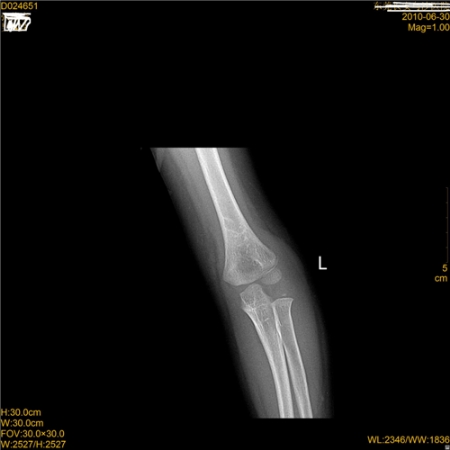

标题: PED3327:外伤!

左肱骨干骺端外侧见蛋壳样骨片,考虑骨折,结合临床。

肱骨髁线样低密度影,重影?建议对侧对比

小儿孟氏骨折,ⅲ型(内收型)。尺骨上端青支骨折,向桡侧隆凸,桡骨小头向桡侧半脱位。此型易误诊。

左肱骨外髁骨折可能,建议双侧对比。

4岁幼儿,应该出肱骨小头、桡骨小头2个骨骺核,右侧桡骨小头骨化中心未出属正常。

左侧肘关节外侧软组织肿胀明显,外侧髁“双边征”,考虑肱骨外侧髁低位髁上骨折,关节无脱位(桡骨小头连线正常)。

有无脱位战友可以参考下图做连线看看。

左侧低位髁上骨折,支持!

左肱骨外侧髁骨折这是肯定的,无脱位。

左肱骨外髁骨折(骺离骨折),非髁上骨折

要小心,动态功能位观察,这种最容易漏诊且预后不良,容易扯皮啊。